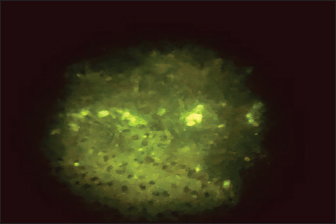

Direct fluorescent antibody technique (DFAT) carried out on brain impression smears from dead mice showed strong positive results represented by apple green spots confirming the presence of rabies (Fig. 2) with 90% positivity (9 out of 10 brain smears diluted up to 1:10,000 within 1–1.5 hours. A negative brain smear showed a negative reaction (Fig. 3) as a dark background. Application of DFAT on BHK-21 cell line inoculated with brain suspensions of infected mice showed intracytoplasmic apple green reactions in nine out of nine (100%) (Fig. 4), while normal cell culture did not show any fluorescent reaction (Fig. 5). This test needs 3–5 days to infect the cells and their preparation for DFAT.

Fig. 3. Negative DFAT carried out on brain impression of healthy mice.

The FITC-labeled antibodies to RABV are employed in the direct fluorescent antibody test, which is the gold standard for routine sensitive and specific lyssavirus postmortem identification (Mayes and Rupprecht, 2015). The FA test is also the most popular way to diagnose rabies infection in both humans and animals since it is reliable and results are frequently available within 30 minutes of receiving the specimen (WHO, 2018). In this study, the DFAT carried out on brain impressions of dead experimentally infected mice and infected BHK21 cell lines showed strong positive results with 90% and 100%, respectively, within 1–1.5 hours.